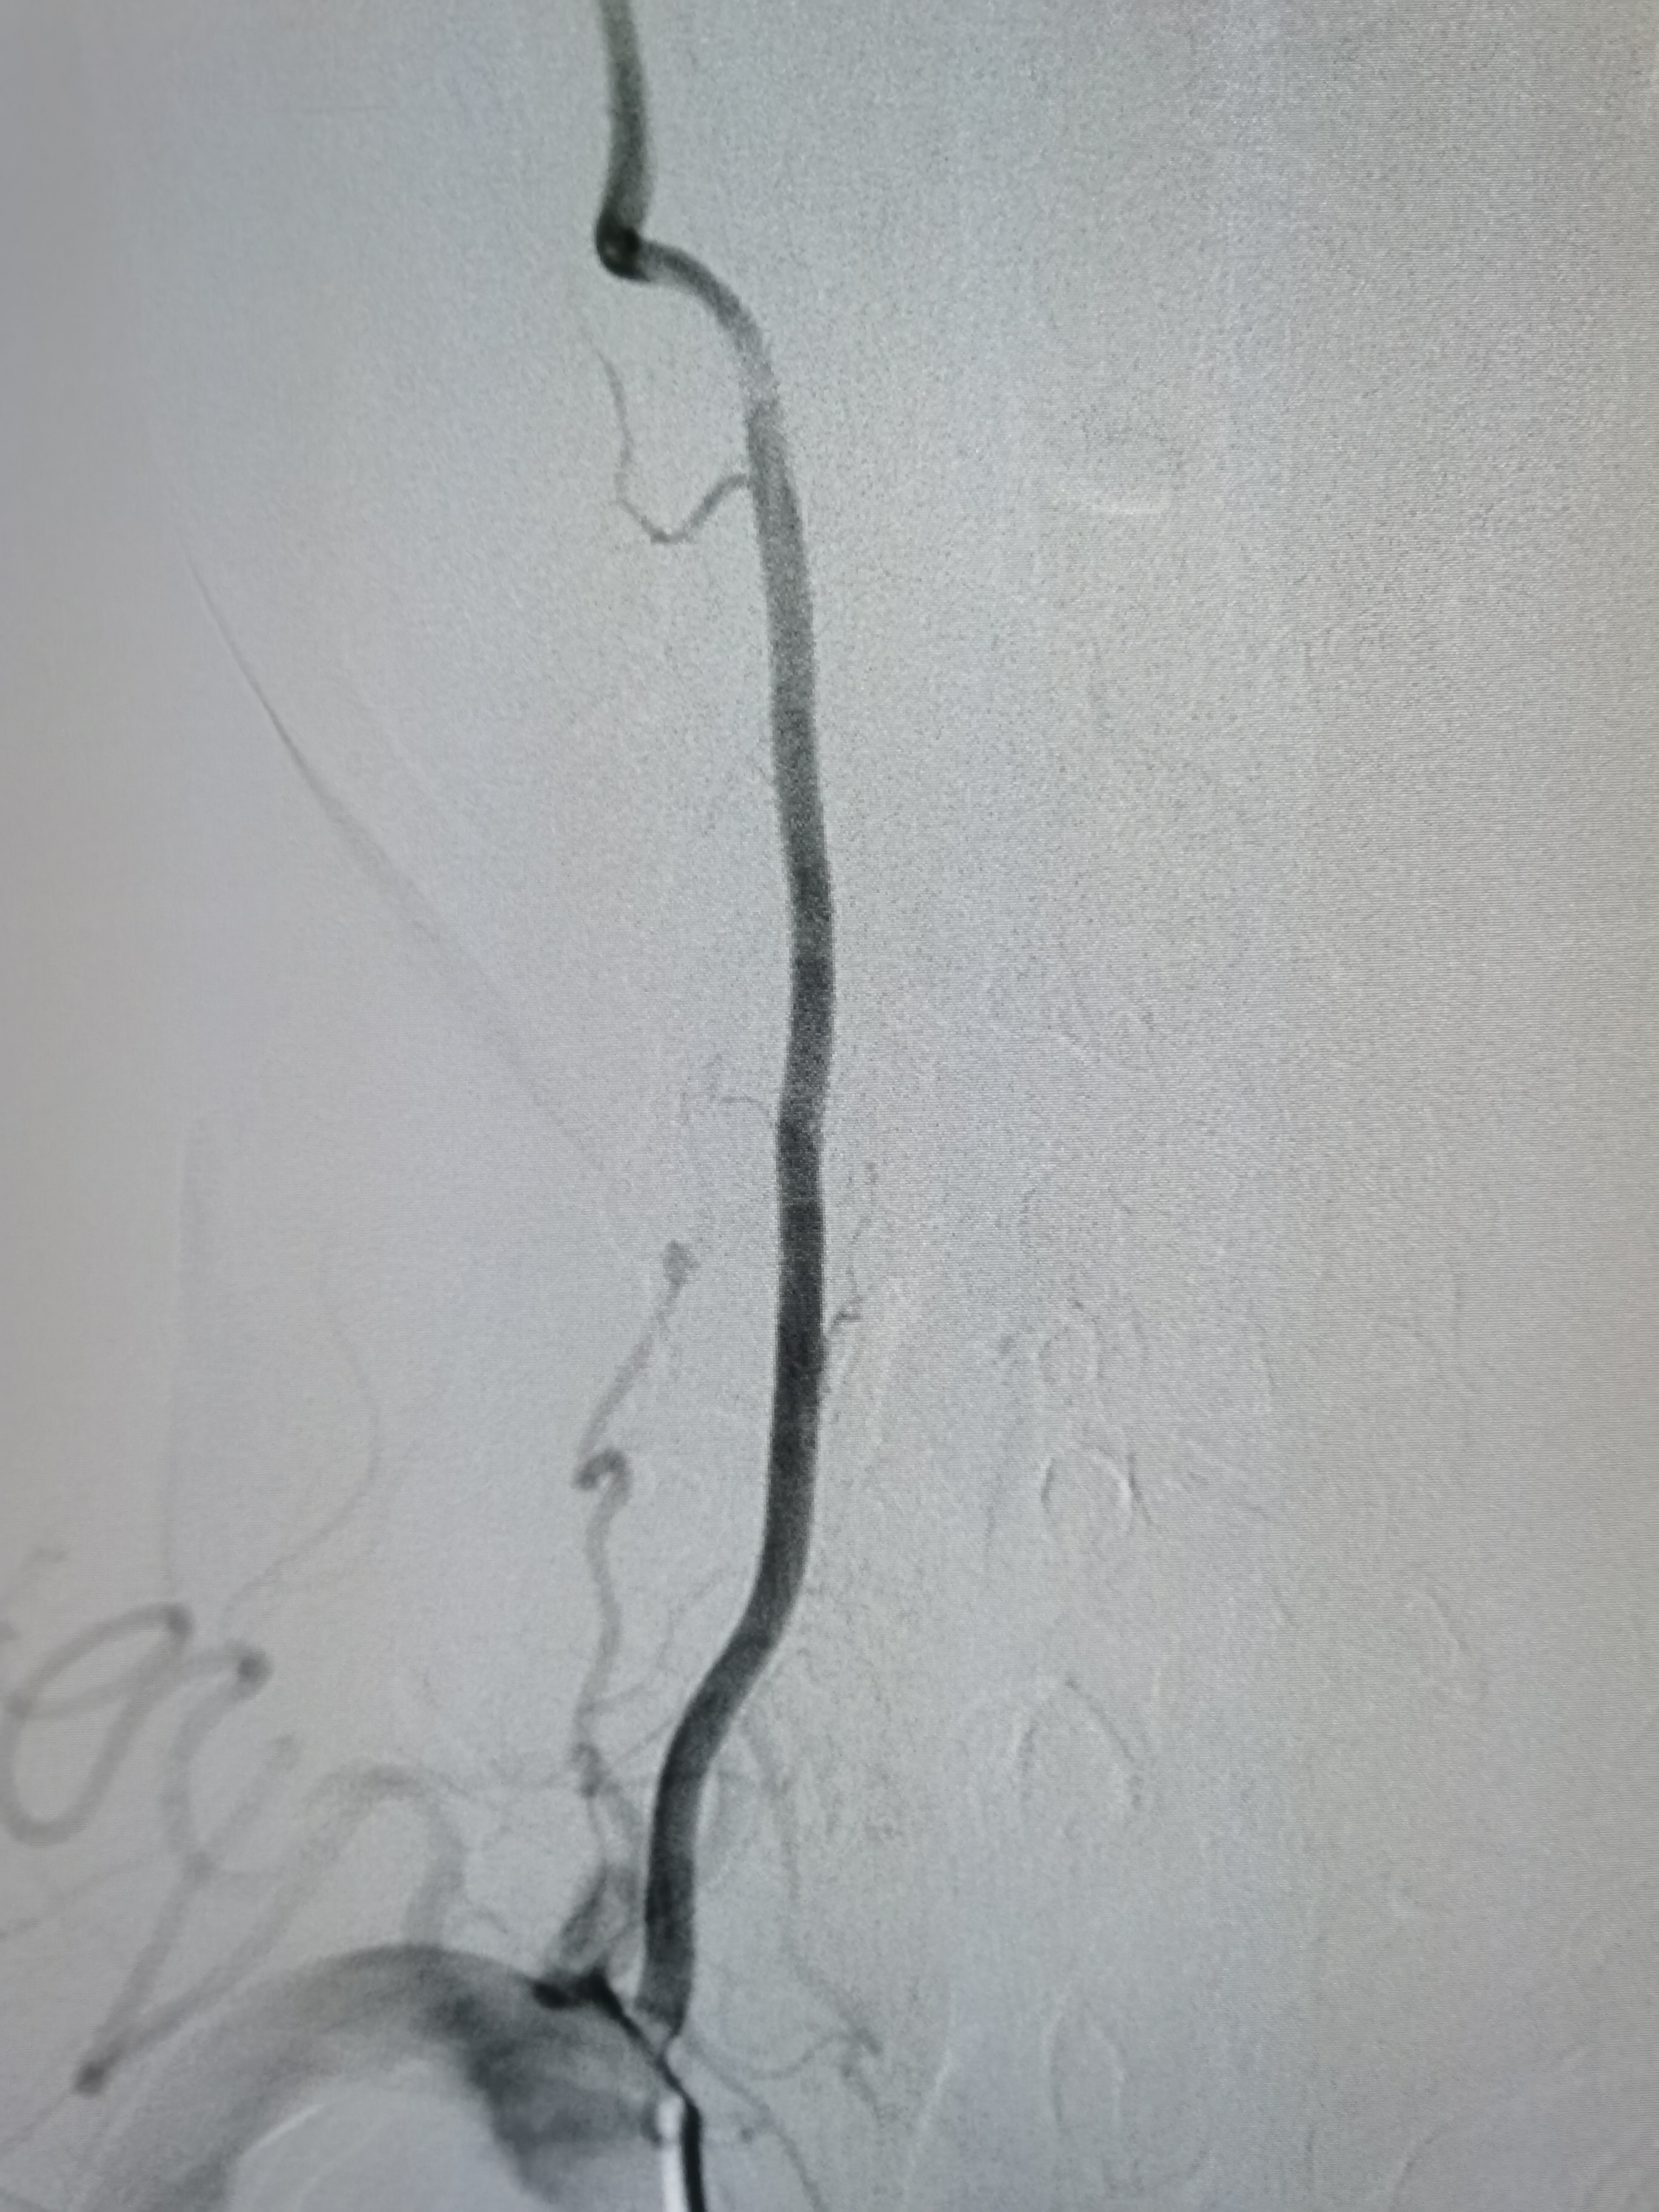

右侧颈内动脉起始部粥样硬化斑块形成。

左侧颈内动脉起始部正常。